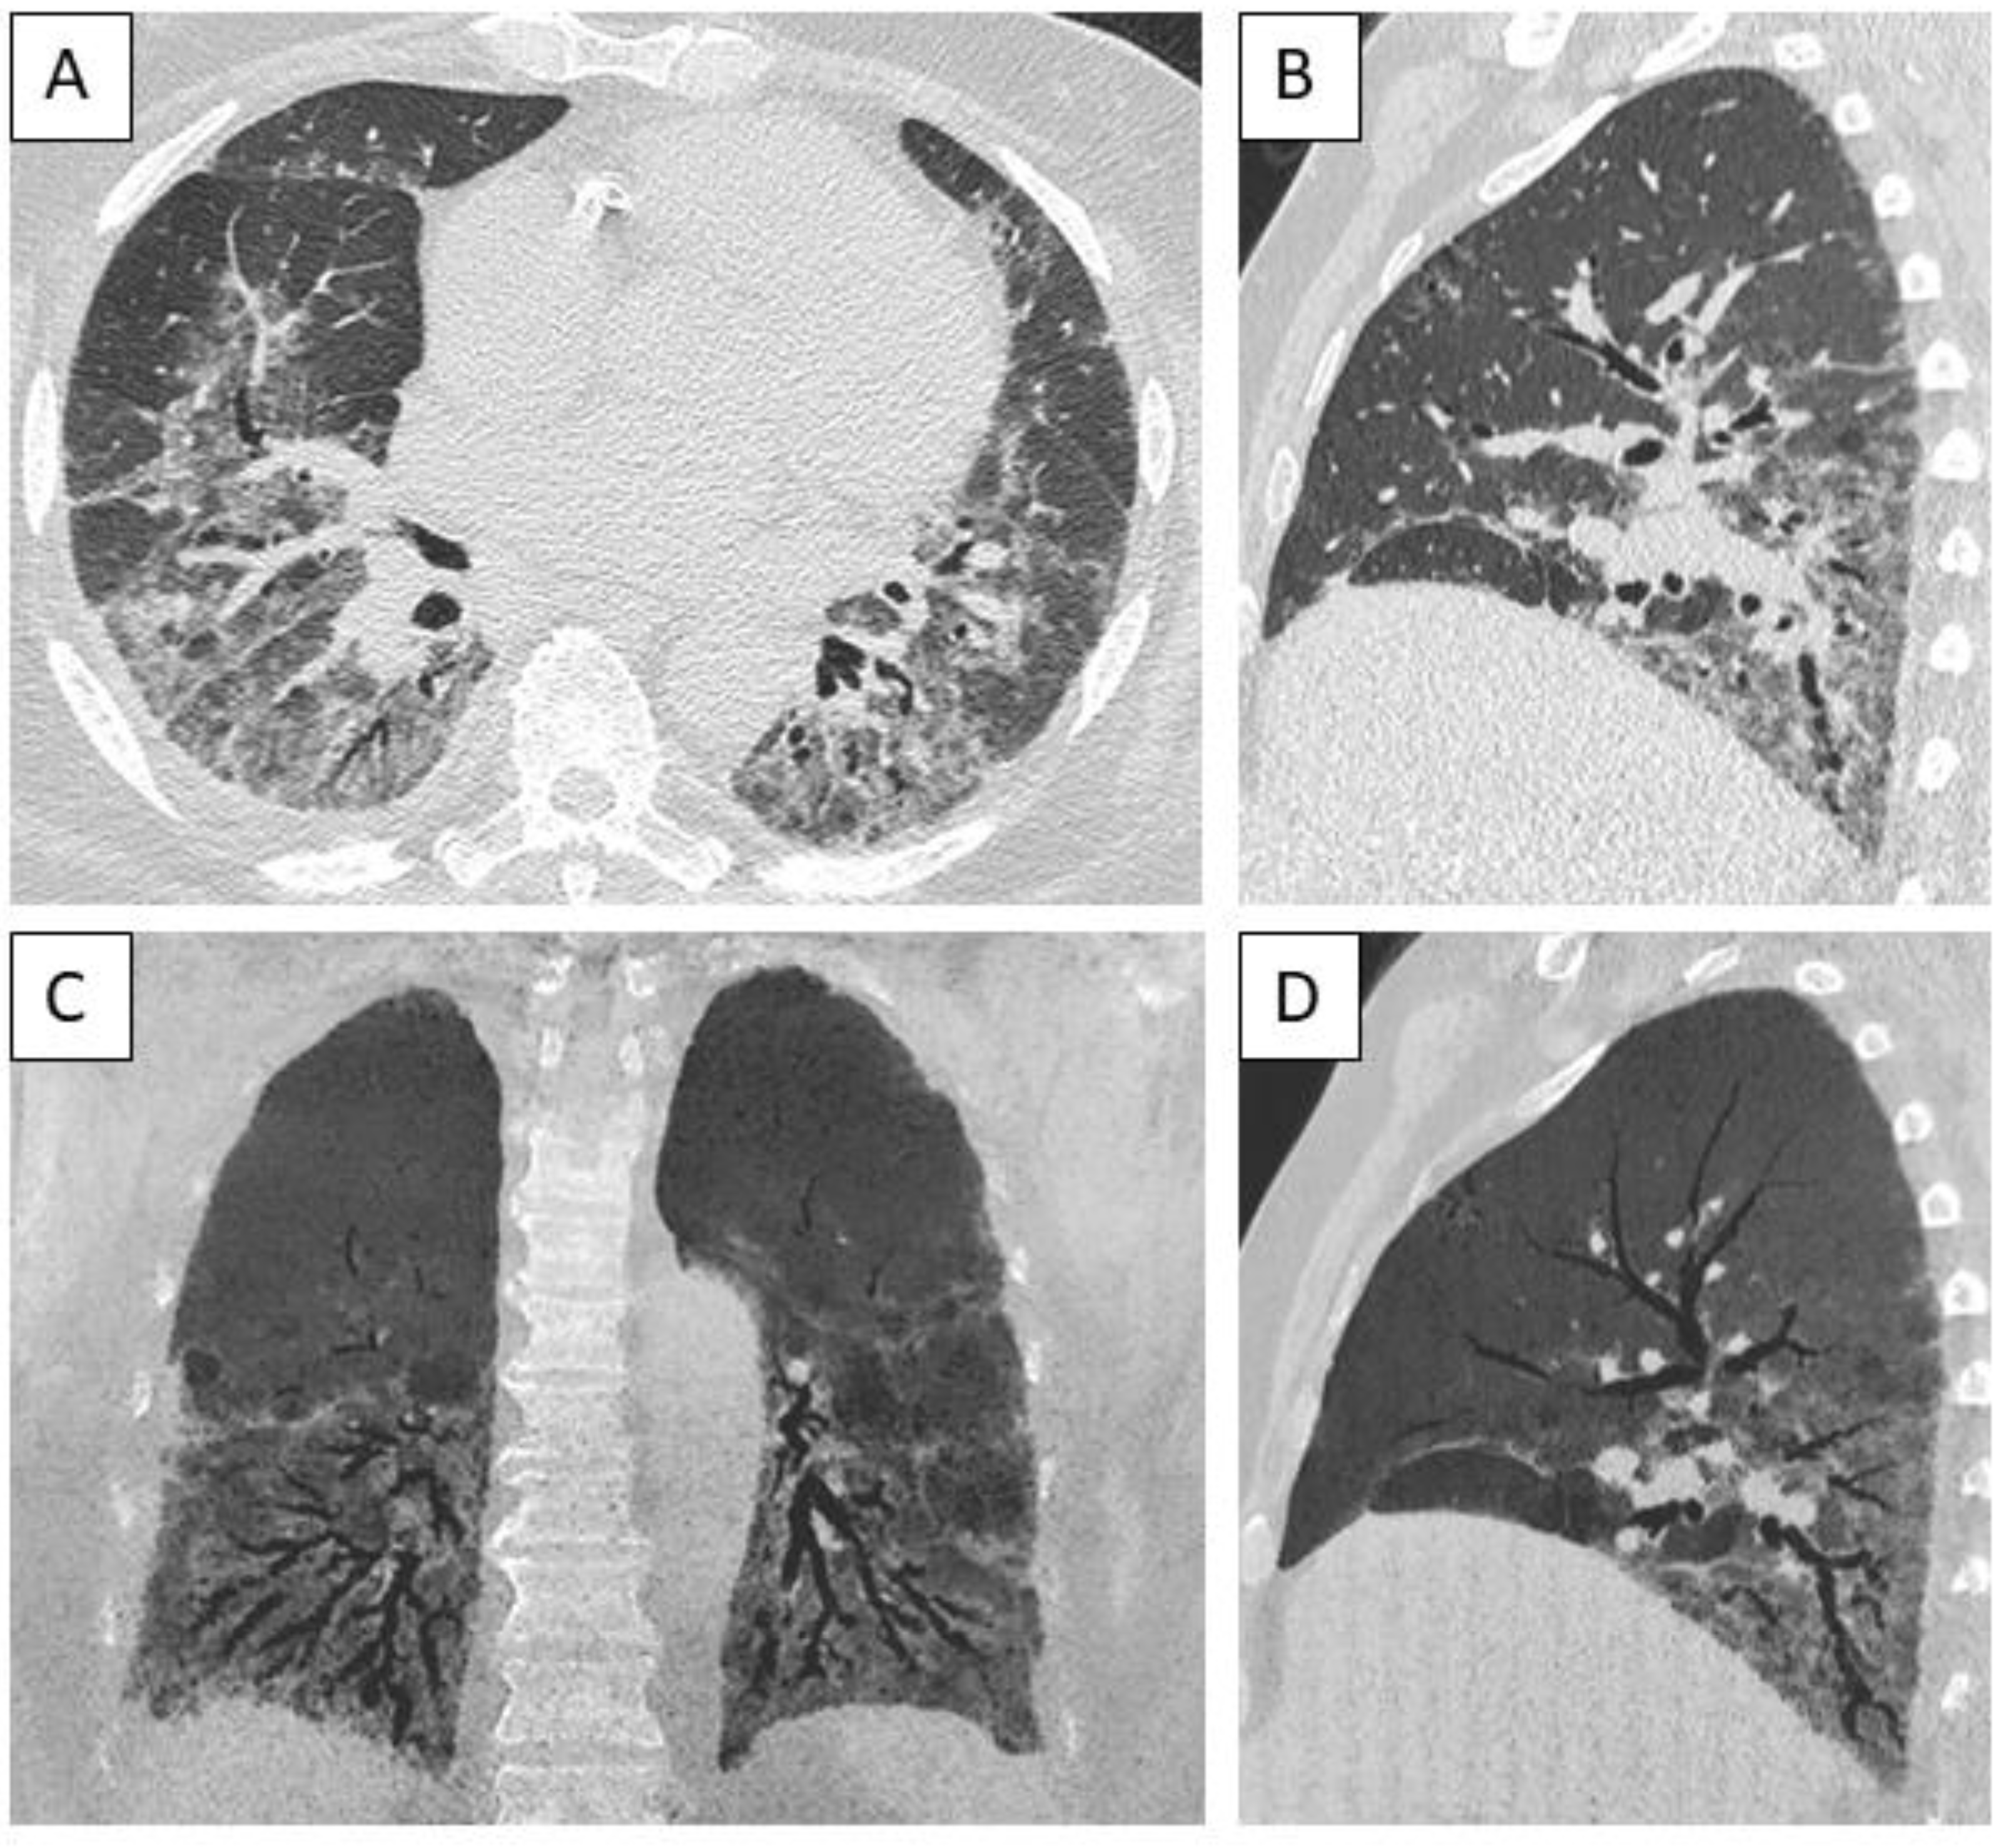

The most frequent radiological pattern was nonspecific interstitial pneumonia (NSIP), identified in 10 cases (53%); two additional cases had a pattern of NSIP / organizing pneumonia overlap (Figure 3). No significant difference was observed in the distribution of patterns according to the underlying diagnosis of autoimmune disease (data not shown).

Figure 3. Computed tomography of a male patient with anti-Ku antibodies demonstrating a pattern of fibrotic nonspecific interstitial pneumonia. A: axial view of lower part of the lungs, demonstrating diffuse distribution of ground glass opacities, reticulation, bronchiectasis and bronchiolectasis. B: sagittal view showing apicobasal distribution; C: coronal view, minimal intensity projection 13 mm. D: sagittal view, minimal intensity projection 13 mm.